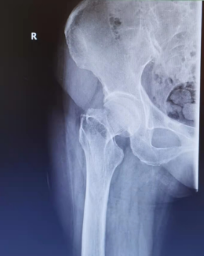

全髋关节置换(股骨颈骨折、股骨头缺血坏死,髋关节发育不良及髋关节退变性关节炎等疾病)

双动全髋关节置换术